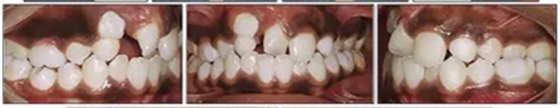

咬合關(guān)系:右側(cè)磨牙有II類關(guān)系傾向,尖牙關(guān)系II類;左側(cè)磨牙關(guān)系完全I(xiàn)I類,尖牙關(guān)系I類。上頜雙側(cè)反合,中線稍有偏離。覆合、覆蓋減少。上頜中切牙向腭裂側(cè)旋轉(zhuǎn),上頜右側(cè)尖牙頰側(cè)異位萌出,雙側(cè)乳尖牙仍存在?;颊呱项M弓嚴(yán)重?fù)頂D(擁擠度約10mm),下頜弓輕度擁擠4mm(擁擠度約4mm)(圖1 ;圖2)。牙周檢查良好。